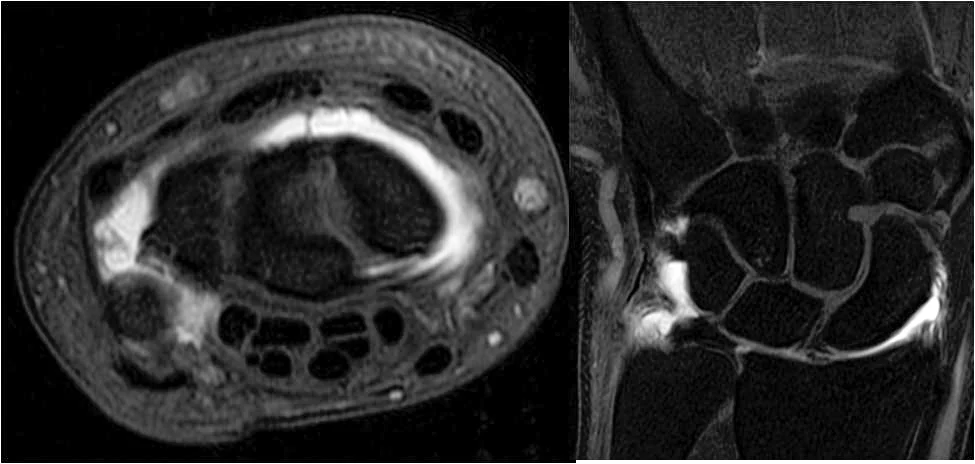

Musculoskeletal Radiology →

The mission of the Musculoskeletal Radiology Fellowship Program at UMass Chan Medical School is to provide fellows with high-level, state-of-the-art training in musculoskeletal radiology, and to produce skilled and competent musculoskeletal radiologists who will succeed in both academic and private practices.